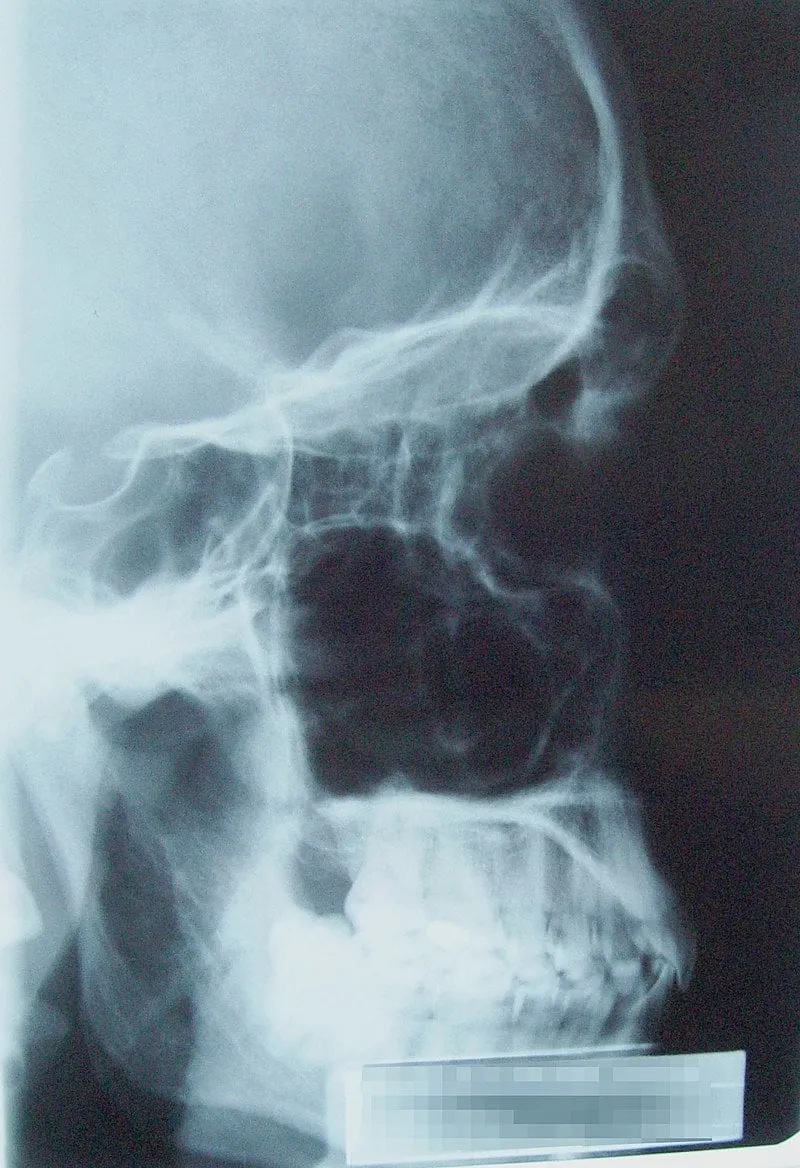

Photo : sinus paranasaux (en noir sur la radiographie car remplis d'air)

La sinusite est une inflammation de la muqueuse d'une ou de plusieurs cavités sinusiennes, dites sinus qui sont des cavités présentes dans les os du visage et du crâne. Vous faites des sinusites régulièrement ? Attention à votre alimentation ! Voici les habitudes alimentaires conseillées... ou non.